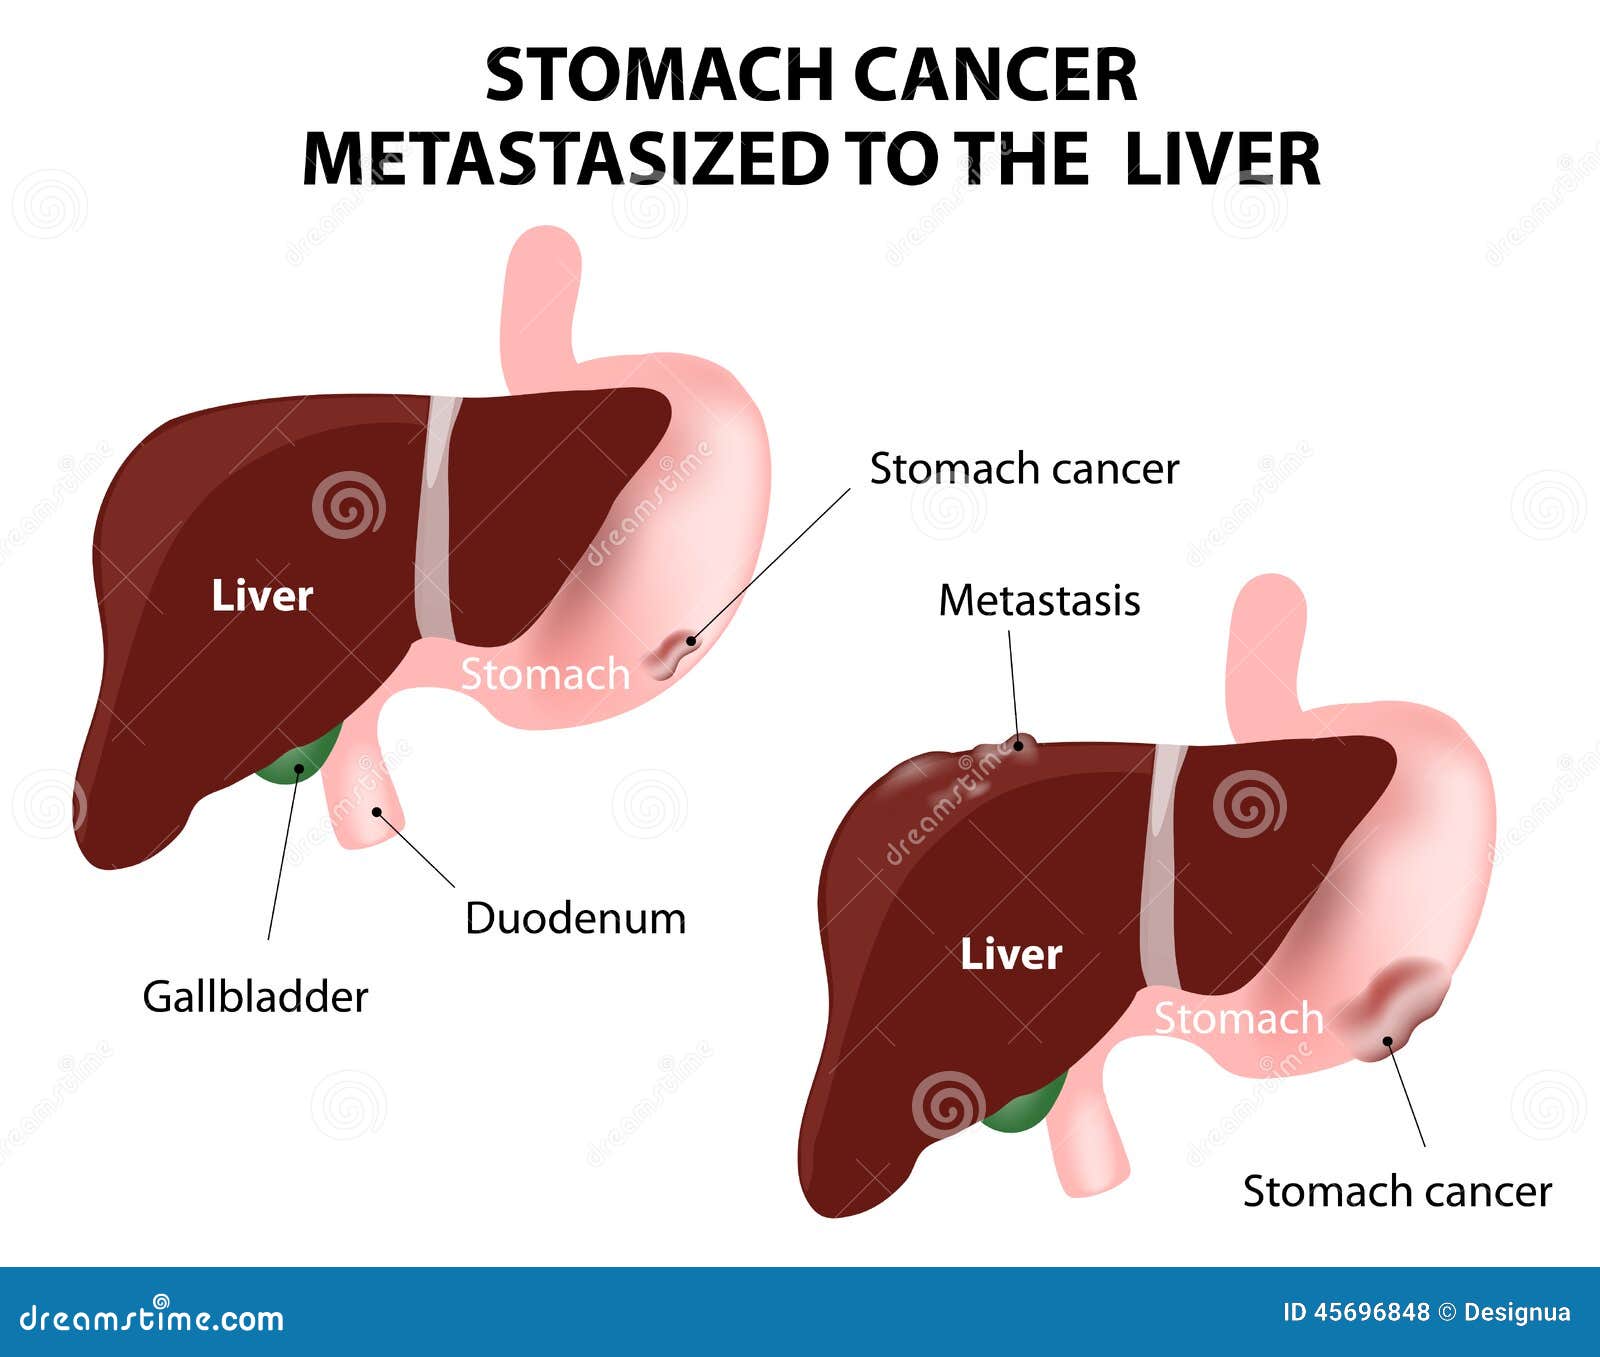

Stage 4 Stomach Cancer. What is advanced cancer? | by Zeeva Clinic | Medium

Stage 4 Stomach Cancer. What is advanced cancer? | by Zeeva Clinic | Medium

Stage 4 Stomach Cancer. What is advanced cancer? | by Zeeva Clinic | Medium